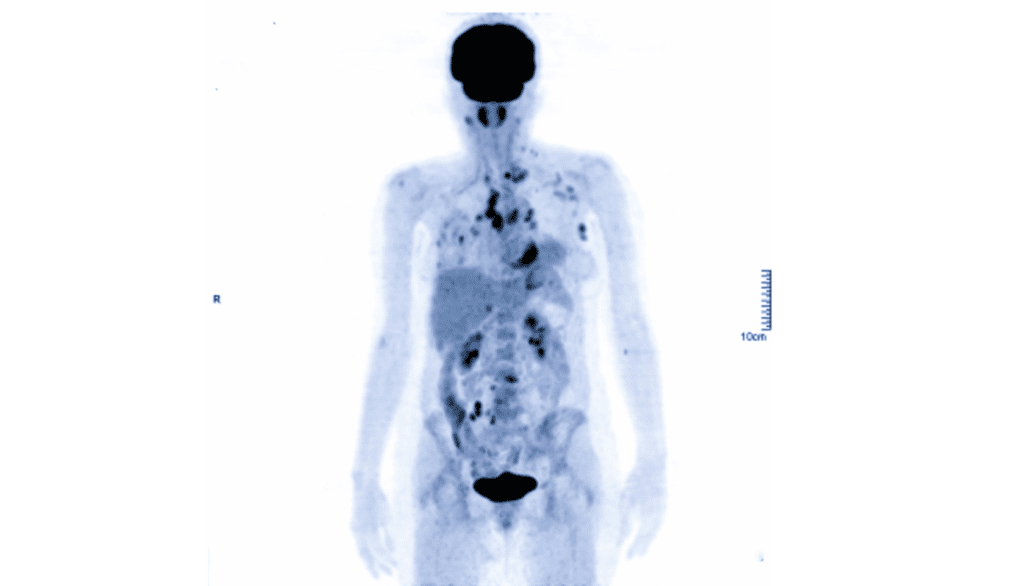

• Medical Tracers – these are radioactive medicines that are used to either treat a disease or take an image. For example, the image on the right shows a PET image. This image was taken by injecting a radioactive medical tracer into the body and then detecting the radiation emitted by the tracer.